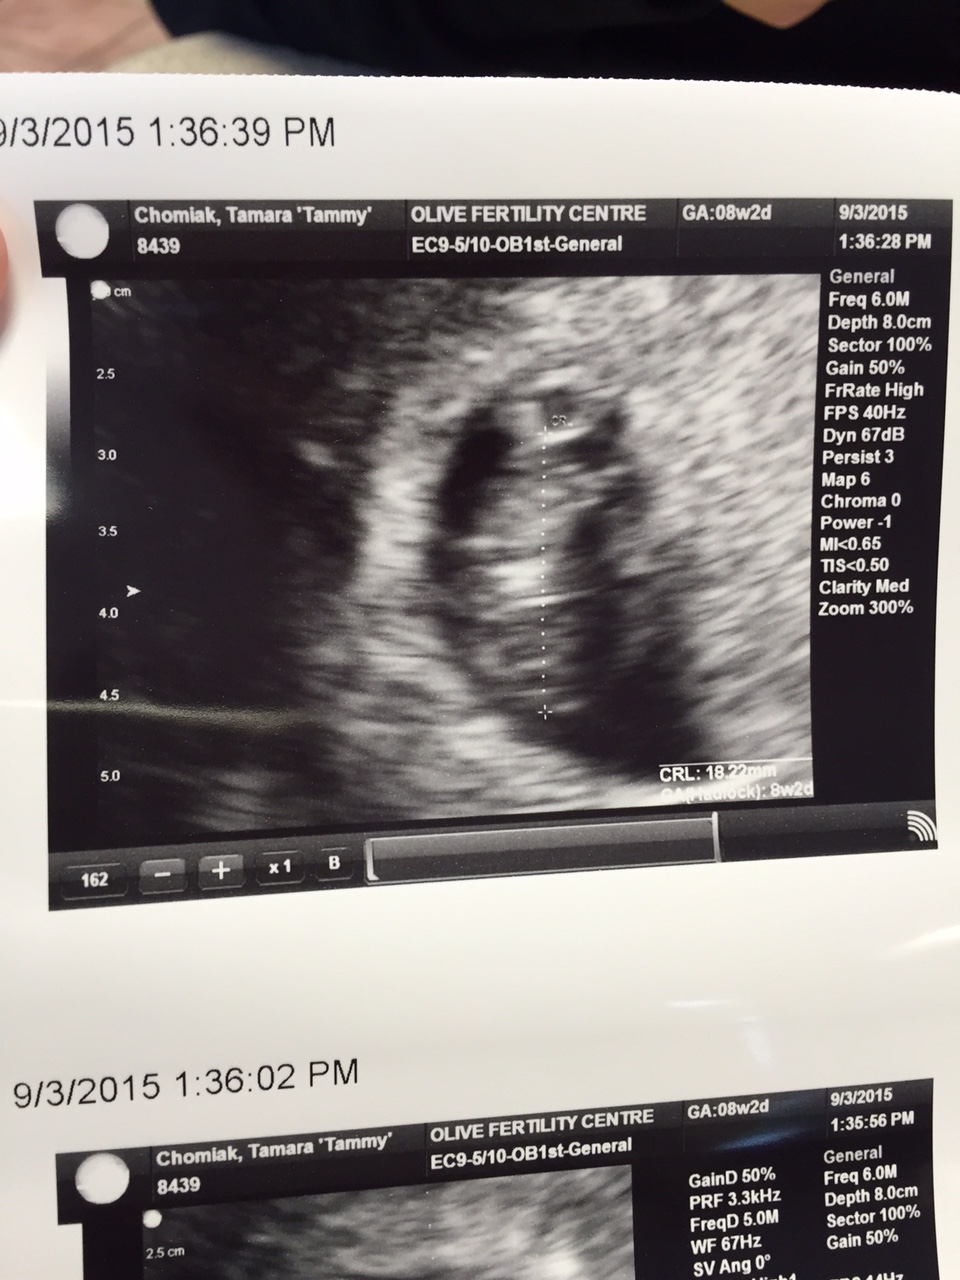

8 week ultrasound: